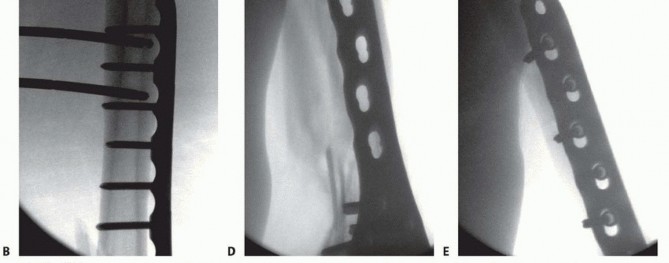

### FIG 3 • A. Patient with a grade IIIA open distal femur with extruded fragment; the “extension” of the femoral condyles is outlined. B. Patient with a distal femur fracture with intercondylar extension showing the subtle rotational deformities of the individual condyles. C. The muscle forces are shown on the distal femur, as is the femoral artery and vein entering the canal of Hunter (arrow). The adductor magnus inserts on the adductor tubercle, leading to a varus deformity of the distal segment. D. A lateral image of the same patient with the popliteal artery and tibial nerve drawn in to show the relative proximity to the fracture ends. 468

* FIG 2 • Mechanical and anatomic axes of the lower extremity; the 9 degrees of valgus at the knee is noted. The neurovascular structures about the knee are at risk when an injury of the distal femur occurs. At the canal of Hunter, roughly 10 cm proximal to the knee on the medial side, the superficial femoral artery enters the popliteal fossa (see FIG 3C). Posterior to the knee, both the popliteal artery and the tibial nerve are at risk at the fracture site ( FIG 3D). ## PATHOGENESIS As mentioned, there is a bimodal distribution in terms of age in the epidemiology of distal femur fractures. This relates to the mechanism of injury. High-energy and low-energy injuries occur. High-energy injuries usually are from motor vehicle accidents and occur in the young patient. There is a direct impact onto the flexed knee, such as from the dashboard. These patients often have associated injuries such as a hip fracture or dislocation or vascular or nerve injury. These high-energy injuries generally result in comminuted fractures, mostly of the metaphyseal region. The comminution can be articular as well. Low-energy injuries usually occur in the elderly patient who falls from a standing height. The axial loading is accompanied by either varus or valgus with or without rotation. The osteoporotic bone in these individuals leads to fracture. The fracture pattern can vary from the most simple extra-articular type to the most complex intraarticular injury. Owing to the gastrocnemius complex, an apex posterior deformity of the condyles occurs as the fragments are flexed because of the muscle attachment. ## NATURAL HISTORY Fractures of the distal femur that have intra-articular displacement can lead to severe posttraumatic arthritis if left untreated. Operative treatment has led to a 32% decrease in poor outcomes. 19 ## PATIENT HISTORY AND PHYSICAL FINDINGS Direct physical examination of the knee with a distal femur fracture is limited primarily because of pain and the obvious nature of the injury. The patient presents with a swollen and tender knee after either a fall or some high-energy trauma (motor vehicle or motorcycle accident). A large hemarthrosis is present. Any attempts at range of motion result in severe pain, and significant crepitus is usually noted with palpation. If there is concern for an open knee joint, the joint can be injected after a sterile preparation to see whether the knee joint communicates with any wound. The physical examination is directed primarily at ascertaining the neurovascular status of the lower limb and determining whether any associated injuries exist, especially the hip (see Exam Table for Pelvis and Lower Extremity Trauma, pages 1 and 2). If there are any small wounds or tenting of the skin anteriorly, the fracture should be considered as being open. It is important to check for pulses. If diminished or absent, pulses should be assessed with Doppler. The ankle-brachial indices should be obtained if there is a concern for arterial injury. Any side-to-side difference or value less than 0.9 warrants an arteriogram. Computed tomography (CT) arteriogram has been used with increasing frequency as well in cases where there is concern ( FIG 4). Nerve function should be checked. Sensation and both active dorsiflexion and plantarflexion must be assessed. ## IMAGING AND OTHER DIAGNOSTIC STUDIES The initial imaging study is always plain radiographs. Anteroposterior (AP) and lateral radiographs of the knee should be obtained initially. Traction films should be obtained if there is severe comminution of either the metaphysis or articular surface. This aids in the preoperative planning. 467